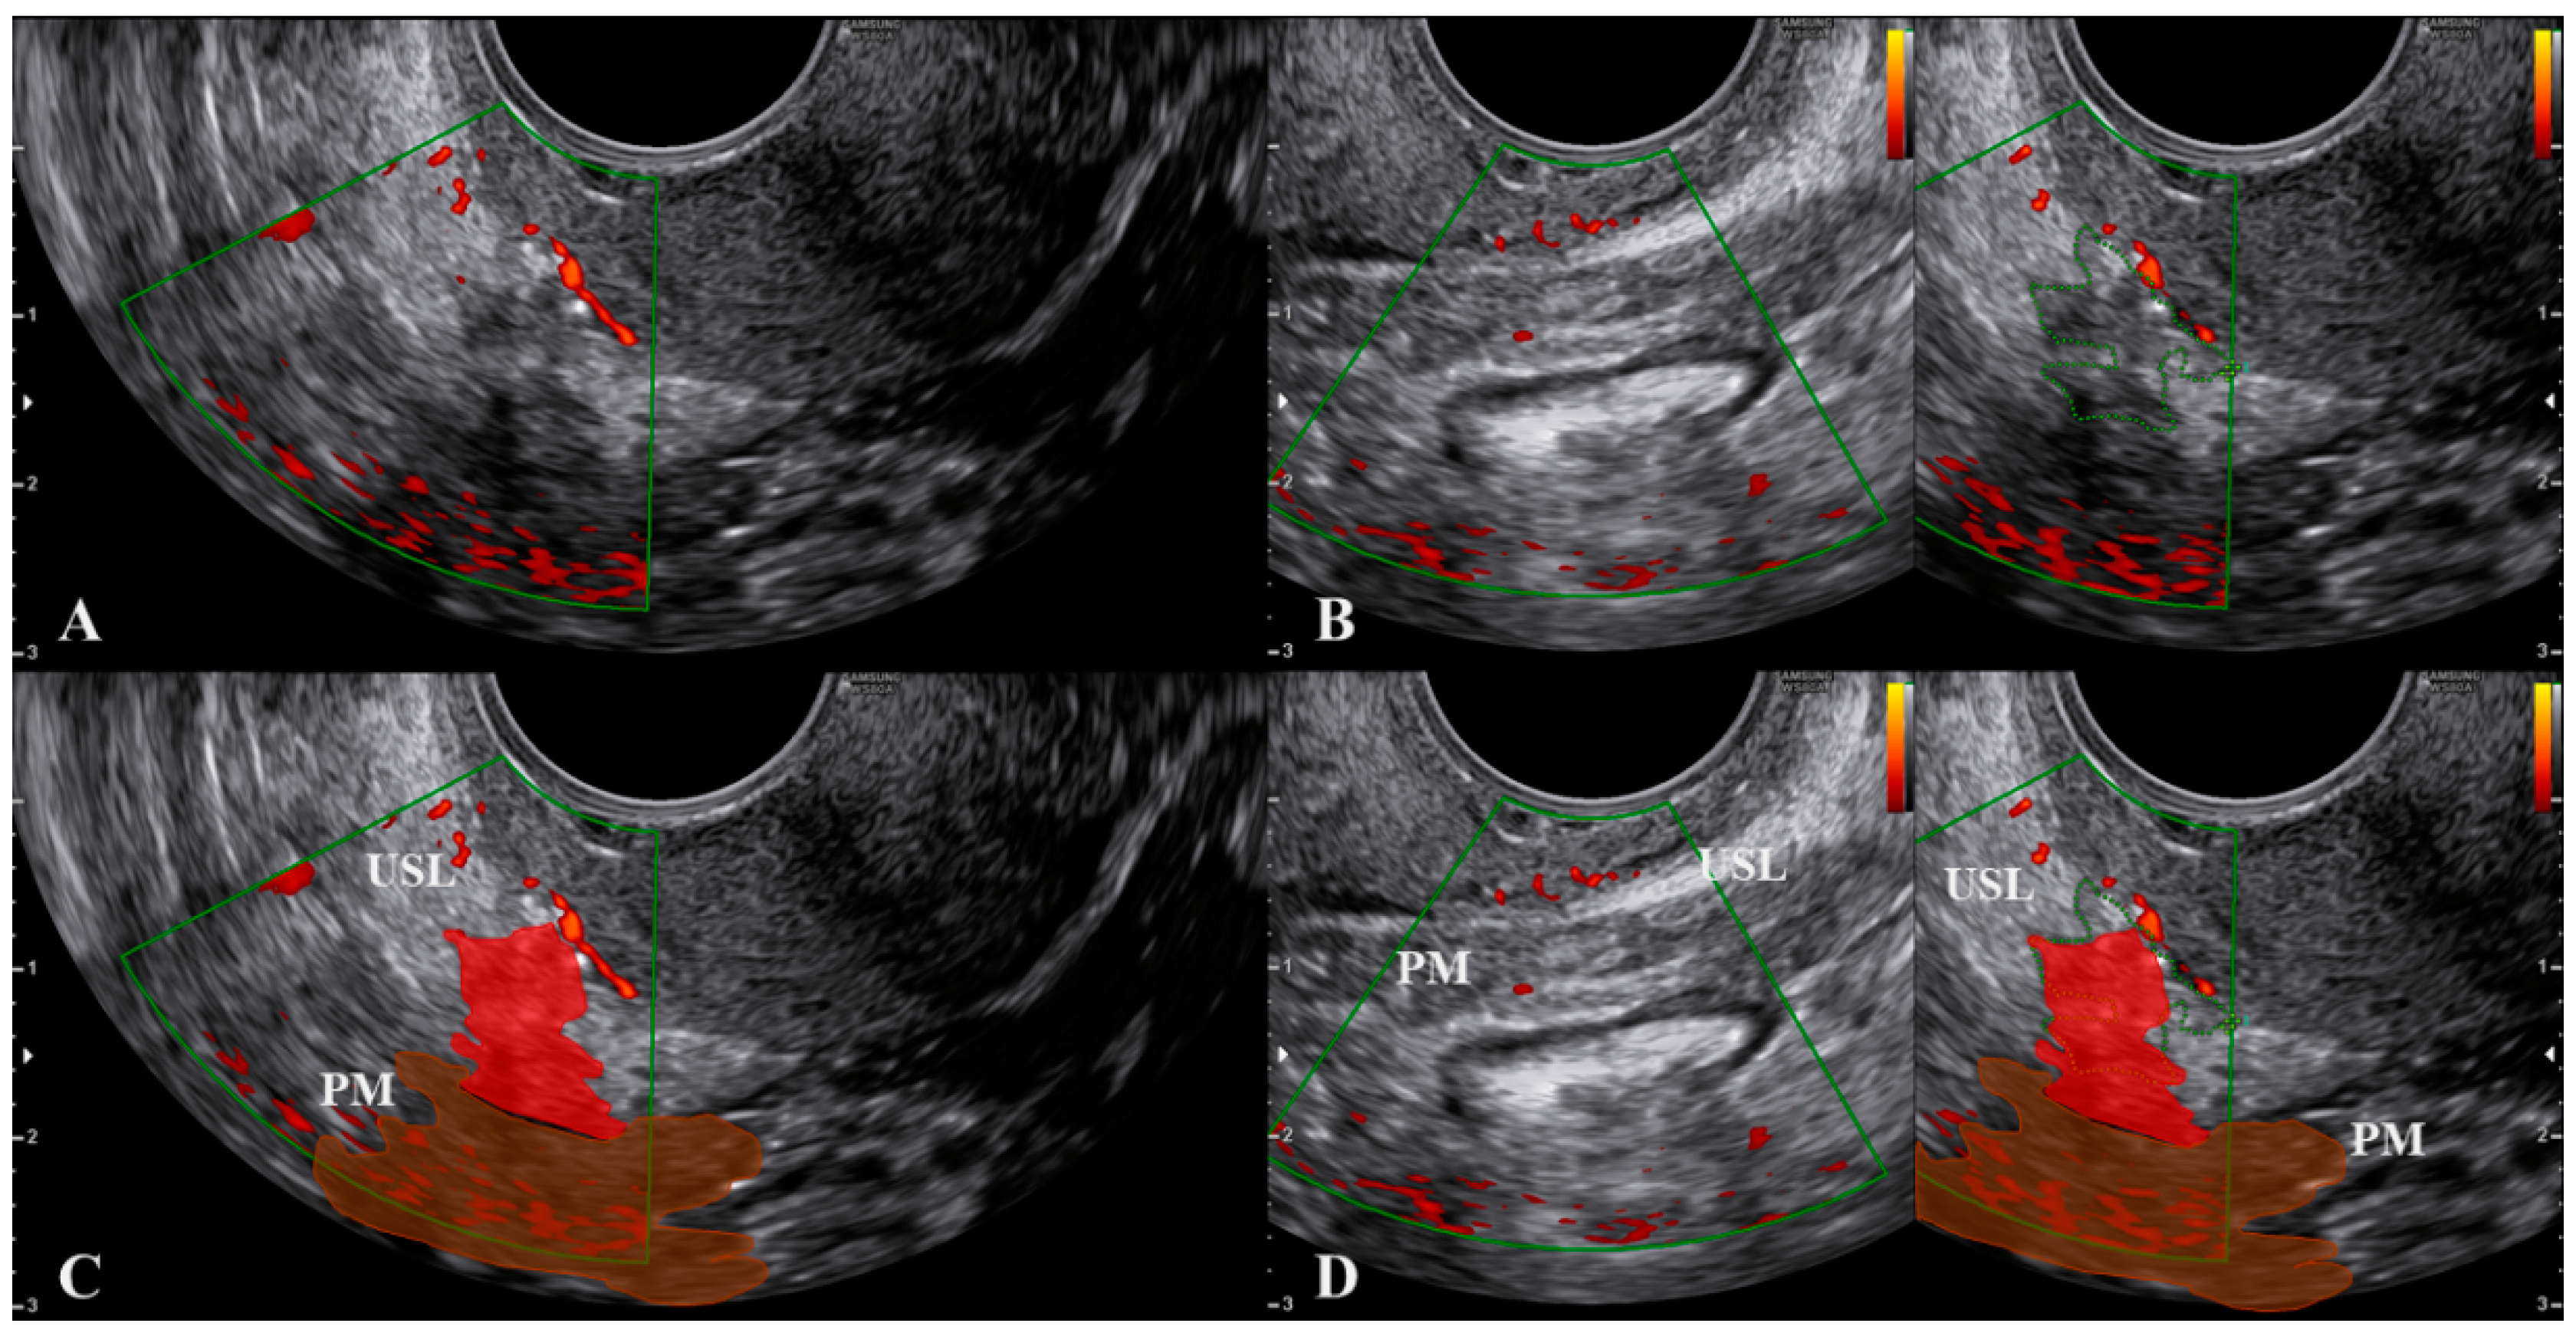

- Scioscia, M.; Virgilio, B.A.; Scardapane, A.; Pontrelli, G. Fusion Imaging: A Novel Diagnostic Tool for Nerve-Sparing Surgery for Deep Infiltrating Endometriosis. J. Minim. Invasive Gynecol. 2020, 27, 246–247. [Google Scholar] [CrossRef]